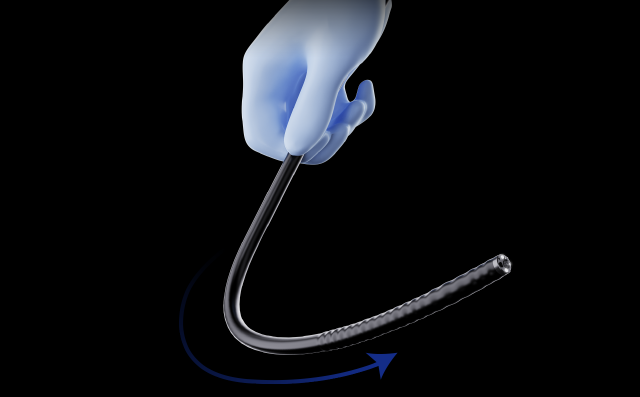

Синхронизация передачи усилияИнерционная конструкция во вводной части колоноскопа. Во время обследования он может передавать толкающие, вытягивающие и вращательные усилия, прилагаемые оператором к рукоятке, на дистальный конец колоноскопа, способствуя лучшему введению в цекум.

Синхронизация передачи усилияИнерционная конструкция во вводной части колоноскопа. Во время обследования он может передавать толкающие, вытягивающие и вращательные усилия, прилагаемые оператором к рукоятке, на дистальный конец колоноскопа, способствуя лучшему введению в цекум. Регулируемая жесткостьВводная трубка колоноскопа имеет функцию многоуровневой регулировки мягкости и жесткости.Вращая регулировочное кольцо, можно изменять мягкость и твердость вводимой части в соответствии с требованиями эндоскопии различных отделов толстой кишки, как того требуют врачи-клиницисты.

Регулируемая жесткостьВводная трубка колоноскопа имеет функцию многоуровневой регулировки мягкости и жесткости.Вращая регулировочное кольцо, можно изменять мягкость и твердость вводимой части в соответствии с требованиями эндоскопии различных отделов толстой кишки, как того требуют врачи-клиницисты. Эластичный изгибВо время эндоскопических процедур он может адаптироваться к различным изгибам толстой кишки. Способен саморегулироваться и поворачивать корпус эндоскопа к просвету в таких областях, как изгиб селезенки и печеночный изгиб, что уменьшает необходимость манипуляций с эндоскопом и повышает комфорт пациента.

Синхронизация передачи усилия. Вводная часть колоноскопа оснащена инерционной конструкцией, которая обеспечивает прямую передачу механического усилия от рук врача к дистальному концу. Это значит, что все движения — толкание, вытягивание и вращение — передаются без запаздывания и искажений. Такая конструкция повышает управляемость аппарата, особенно в сложных анатомических условиях, и облегчает продвижение эндоскопа до слепой кишки, снижая дискомфорт пациента и продолжительность процедуры.

Регулируемая жесткость. Колоноскоп оснащён многоуровневой системой регулировки жёсткости вводной трубки. С помощью кольца на корпусе можно плавно изменить степень жёсткости — от более гибкой до более жёсткой. Это позволяет врачу адаптировать поведение эндоскопа под конкретную анатомию пациента и тип вмешательства: при прохождении изгибов — использовать мягкий режим, при необходимости продвижения по прямому участку — увеличить жёсткость для лучшей управляемости.

Эластичный изгиб. Эндоскоп способен автоматически адаптироваться к анатомическим изгибам толстой кишки, включая участки с ограниченной подвижностью — например, селезёночный и печёночный изгибы. Благодаря специальной конструкции изгибающейся части, устройство самонаправляется в просвет, снижая количество необходимых коррекций и уменьшает риск травматизации стенок кишечника. Это особенно полезно при обследованиях с затруднённым прохождением и в работе с пожилыми пациентами.